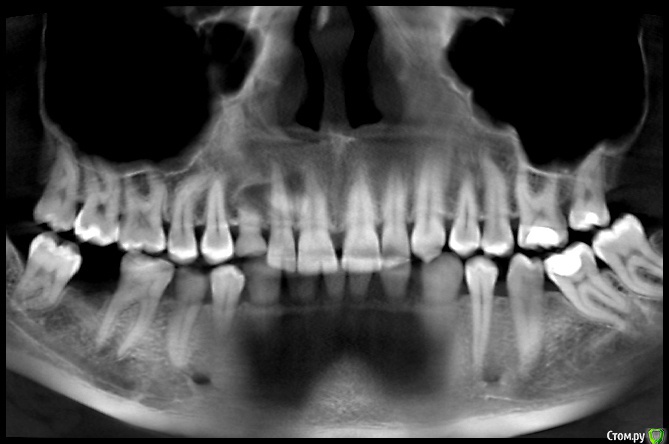

natalie_summerwhile Опубликовано 10 июля, 2017 Автор Поделиться Опубликовано 10 июля, 2017 Во рту вместо клыка молочный Ссылка на комментарий

Qvonti Опубликовано 12 декабря, 2018 Поделиться Опубликовано 12 декабря, 2018 Ортодонтии быть в данном случае!) Ссылка на комментарий